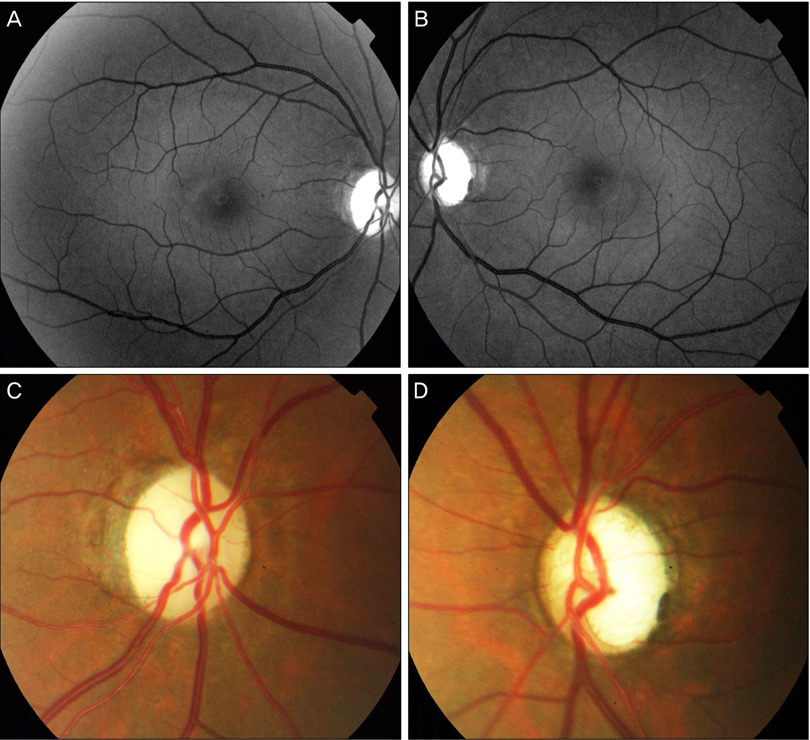

- Fundus findings:

- Optic disc swelling & hyperemia early

- Later: optic disc pallor, retinal arterial narrowing

- Progression to optic atrophy → legal blindness

- OCT: Thinning of retinal nerve fiber layer

- FA (Fluorescein Angiography): Loss of optic disc vasculature